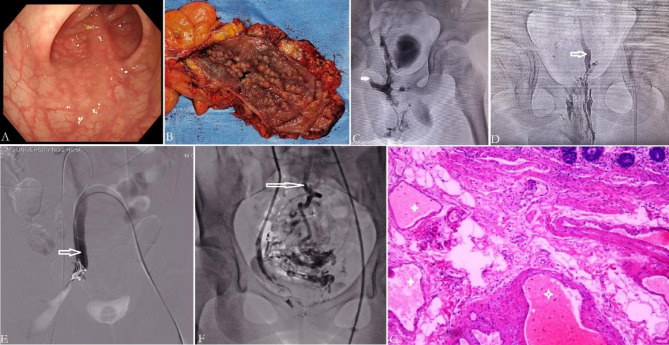

Fig. 2.

Clinical findings in KTS with anorectal and anorectosigmoid VM. VM develops with age, featuring as submucosal reticular phlebectasia in early stage (Panel A), and edematous, stiff and thickened gut by full thickness wall involvement in late stage (Panel B). Active bleeding sites usually can not be identified endoscopically. When sclerotherapy via imaging-guided direct puncture, we can see anorectal VM drains into internal iliac vein (IIV) (Panel C) (arrow), and/or into median sacral vein (Panel D) (arrow). Panel E shows trans-IIV (arrow) sclerotherapy for ablating rectal bleeding. Panel F: In a KTS patient with anorectosigmoid VM, trans-IIV phlebography demonstrated that part of VM drained into the superior rectal vein (arrow), which is indicative of portal vein system involvement. Panel G: Histopathologically, VM are dilated, thin-walled, sponge-like abnormal channels. Extensive venous thrombosis (asterisk) can be identified within the wall of affected colon